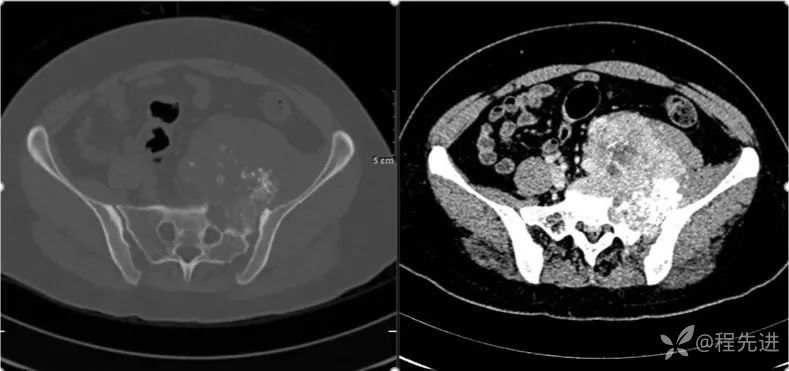

CT

- 是软组织肿瘤累及骨质还是骨肿瘤伴软组织肿块?

- 是软骨基质钙化,还是肿瘤骨?抑或钙化?

- 肿瘤的定性诊断?